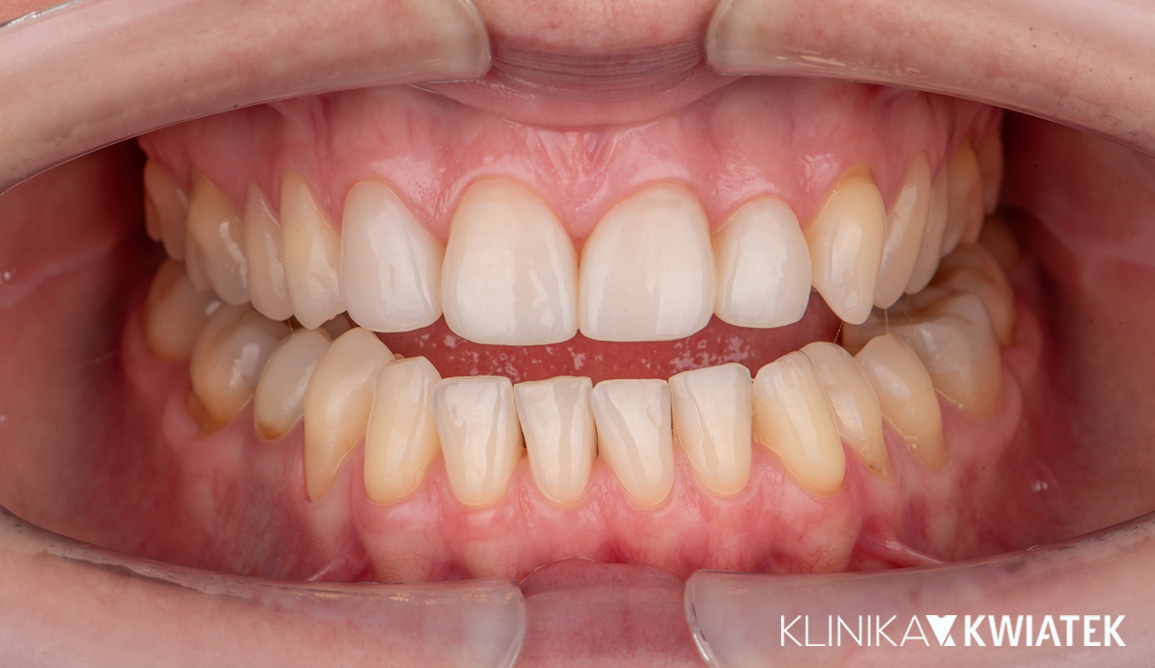

Pacjentka zgłosiła się z licznymi ubytkami, znacznym starciem zębów oraz objawami przeciążenia zgryzu wynikającymi z wieloletniego zaciskania i zgrzytania. Po pełnej diagnostyce przeprowadzono higienizację, leczenie zachowawcze, endodontyczne i szynoterapię, a następnie ortodoncję oraz finalną odbudowę estetyczno-protetyczną wszystkich startych powierzchni zębów. Efektem jest stabilny, zdrowy zgryz, prawidłowa praca stawów oraz harmonijny, trwały i estetyczny uśmiech Pacjentki.

PRZED

PO